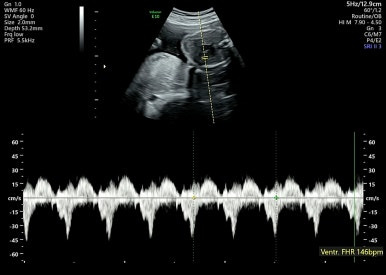

7주 1일차

처음으로 아기를 볼 수 있고, 심장소리를 처음 들을 수 있다!

아기가 1cm 정도 밖에 안되는데 심장소리가 우렁찬게 너무 신비스럽다 :)